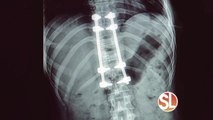

Back pain or sciatica? Call the Ahn Clinic TODAY for a Medical Acupuncture treatment

((SL Advertiser)) To book an appointment at the Ahn Clinic call (480) 515-2000 or visit www.ahnclinic.org